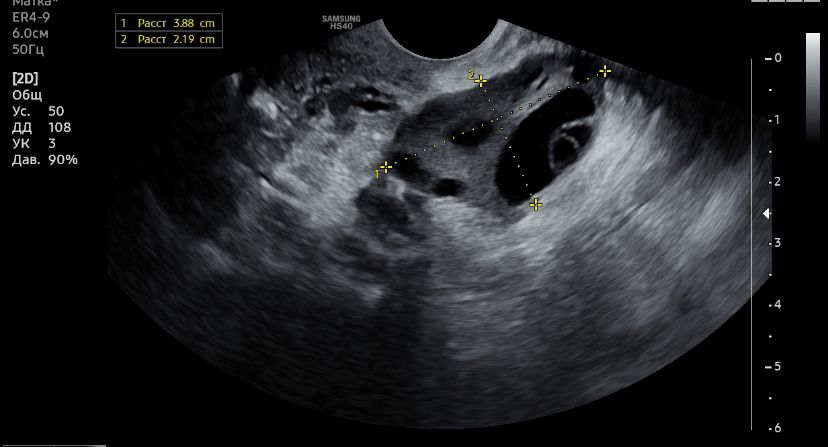

Узи и киста

Девочки, может кто-то разбирается в узи?)

Сказали киста желтого тела, но я не сильно доверяю, до этого она говорила что обычная киста от фоллика